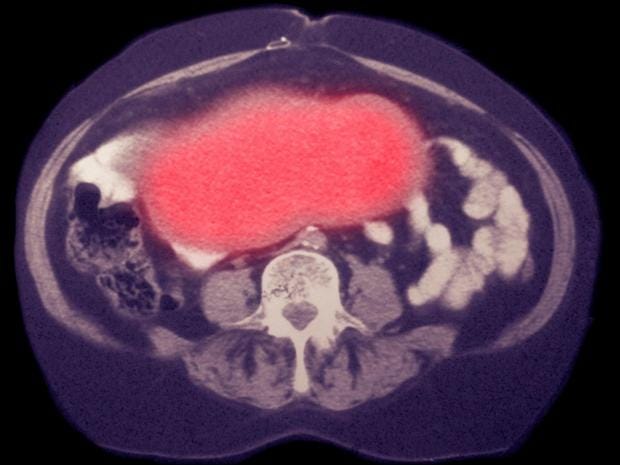

Ovarian cancer has been called a “silent killer” because it is often spotted late and at a deadly stage.

Each year around 7,400 women in the UK are diagnosed with ovarian cancer, and 4,128 die from the disease. Roughly 85 per cent of patients will experience recurrence after treatment.